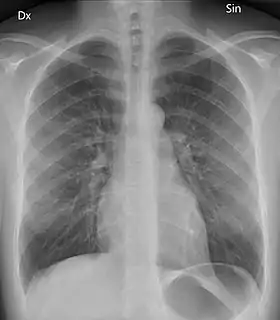

Chest radiographs are used to diagnose many conditions involving the chest wall, including its bones, and also structures contained within the thoracic cavity including the lungs, heart, and great vessels. Conditions commonly identified by chest radiography include pneumonia, pneumothorax, interstitial lung disease, heart failure, bone fracture and hiatal hernia. Typically an erect postero-anterior (PA) projection is the preferred projection. Chest radiographs are also used to screen for job-related lung disease in industries such as mining where workers are exposed to dust.[12]

For some conditions of the chest, radiography is good for screening but poor for diagnosis. When a condition is suspected based on chest radiography, additional imaging of the chest can be obtained to definitively diagnose the condition or to provide evidence in favor of the diagnosis suggested by initial chest radiography. Unless a fractured rib is suspected of being displaced, and therefore likely to cause damage to the lungs and other tissue structures, x-ray of the chest is not necessary as it will not alter patient management.